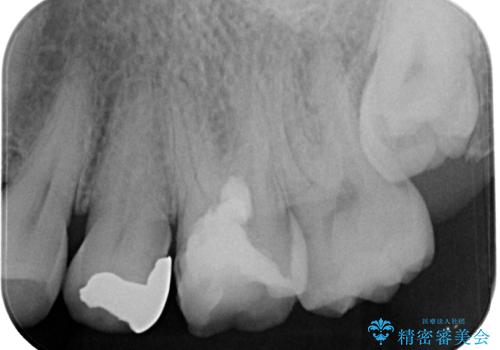

検査の結果、虫歯が非常に深く、通常であれば神経をすべて取り除く抜髄処置が必要な状態でした。

生活歯髄療法は、むし歯が神経の近くまで進行している場合でも、できる限り神経を残すことを目指す治療法です。

従来であれば神経を取る必要があるケースでも、特殊な材料を使用することで神経を保護し、歯の寿命を延ばせる可能性があります。

MTAは

・神経をやさしく保護する

・細菌の侵入を防ぐ

・封鎖性が高く再感染を防ぎやすい

といった特長があり、歯を長く守るために非常に優れた材料です。

神経を残すことができれば、歯は栄養を受け取り続けるため、

将来的な破折リスクの軽減にもつながります。